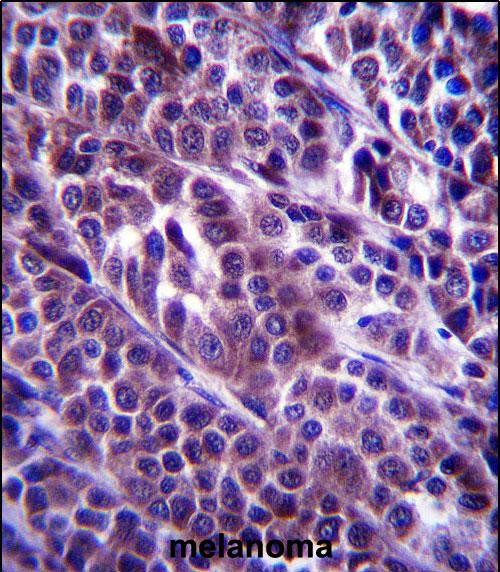

This antibody is commonly used in techniques like Western blotting, immunofluorescence, and immunoprecipitation to study ARMC9 expression, localization, and interactions in cellular and tissue samples. Targeting the N-terminal region ensures specificity for full-length ARMC9 or its major isoforms, distinguishing it from potential degradation products or splice variants. ARMC9 antibodies have been instrumental in elucidating its role in ciliary defects and Wnt/β-catenin signaling dysregulation, particularly in conditions like Joubert syndrome and retinal degeneration. Researchers also utilize these antibodies to explore ARMC9's involvement in tumor progression, as abnormal Wnt signaling is a hallmark of many cancers. Validation data, including knockout controls or peptide competition assays, are essential to confirm antibody specificity in experimental models.